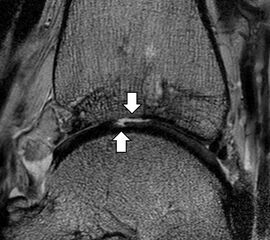

b. T2 fs axial. Infraktion des hinteren Volkmann‘schen Dreiecks (schmale, weiße Pfeile). Hier inserierende, intakte, hintere Syndesmose (breite, weiße Pfeile).

Das Ligamentum tibiofibulare posterius (hintere Syndesmose) verläuft flacher und geht nach kranial in das Ligamentum tibiofibulare interosseus und nach kaudal in das Ligamentum intermalleolare posterius über. Letzteres bildet ein artikuläres Labrum zwischen Trochlea und Talus 9.

Da also die hintere Syndesmose an der posterioren Tibia inseriert, entspricht eine Fraktur oder Infraktion des hinteren Volkmann`schen Dreiecks funktionell einem knöchernen Ausriss des Ligamentum tibiofibulare posterius (Abb. 18 a und b). Aufgrund der Koinzidenz von Syndesmosenläsionen mit Innenbandverletzungen ist bei der Beurteilung gesondert auf solche zu achten.